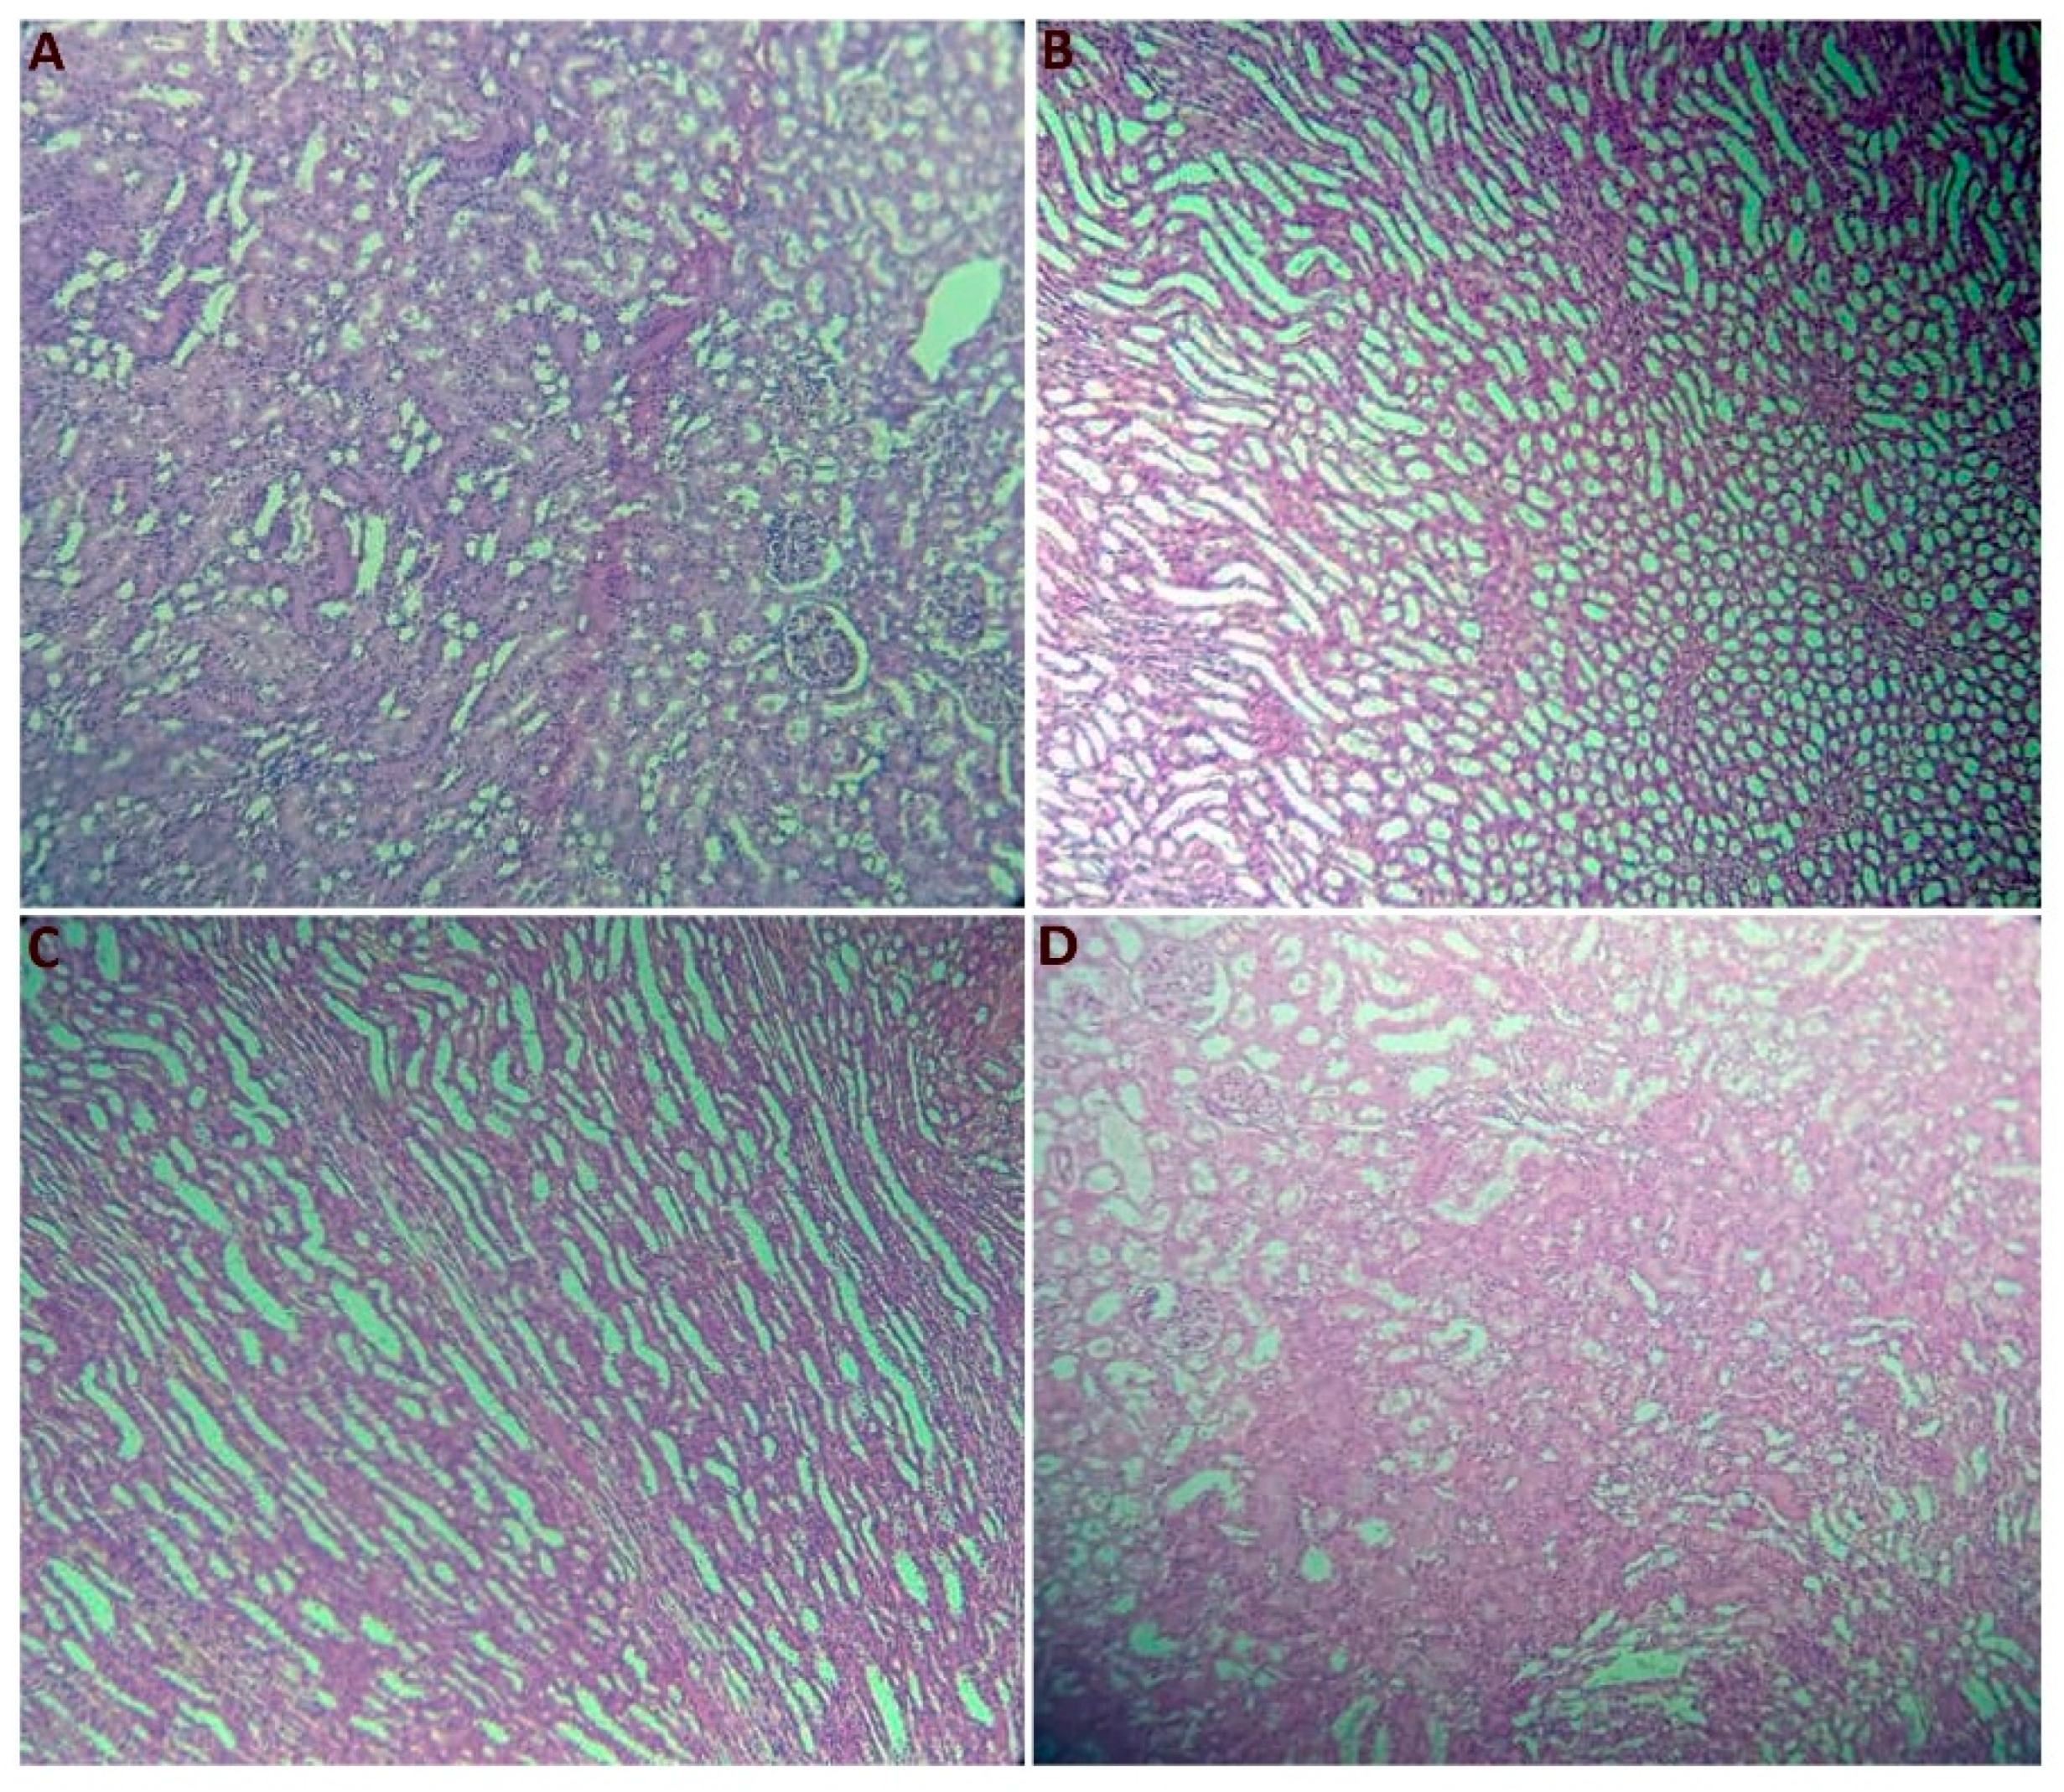

2.2.7. Histological Section Study